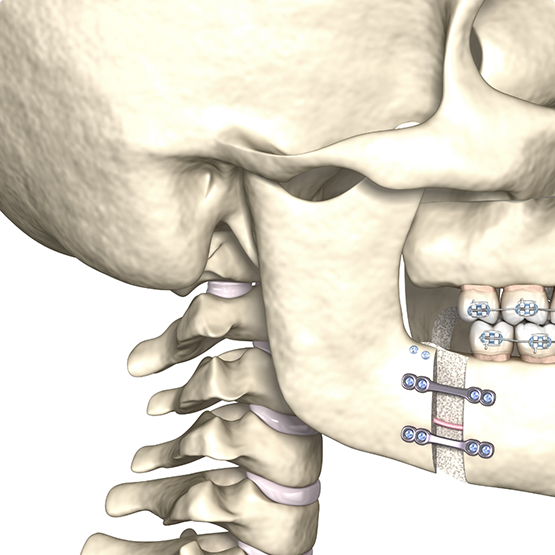

Surgical Case

Patient presented with a class III profile, underbite. The patient underwent orthodontic and surgical treatment. Facial profile showed significant improvement.